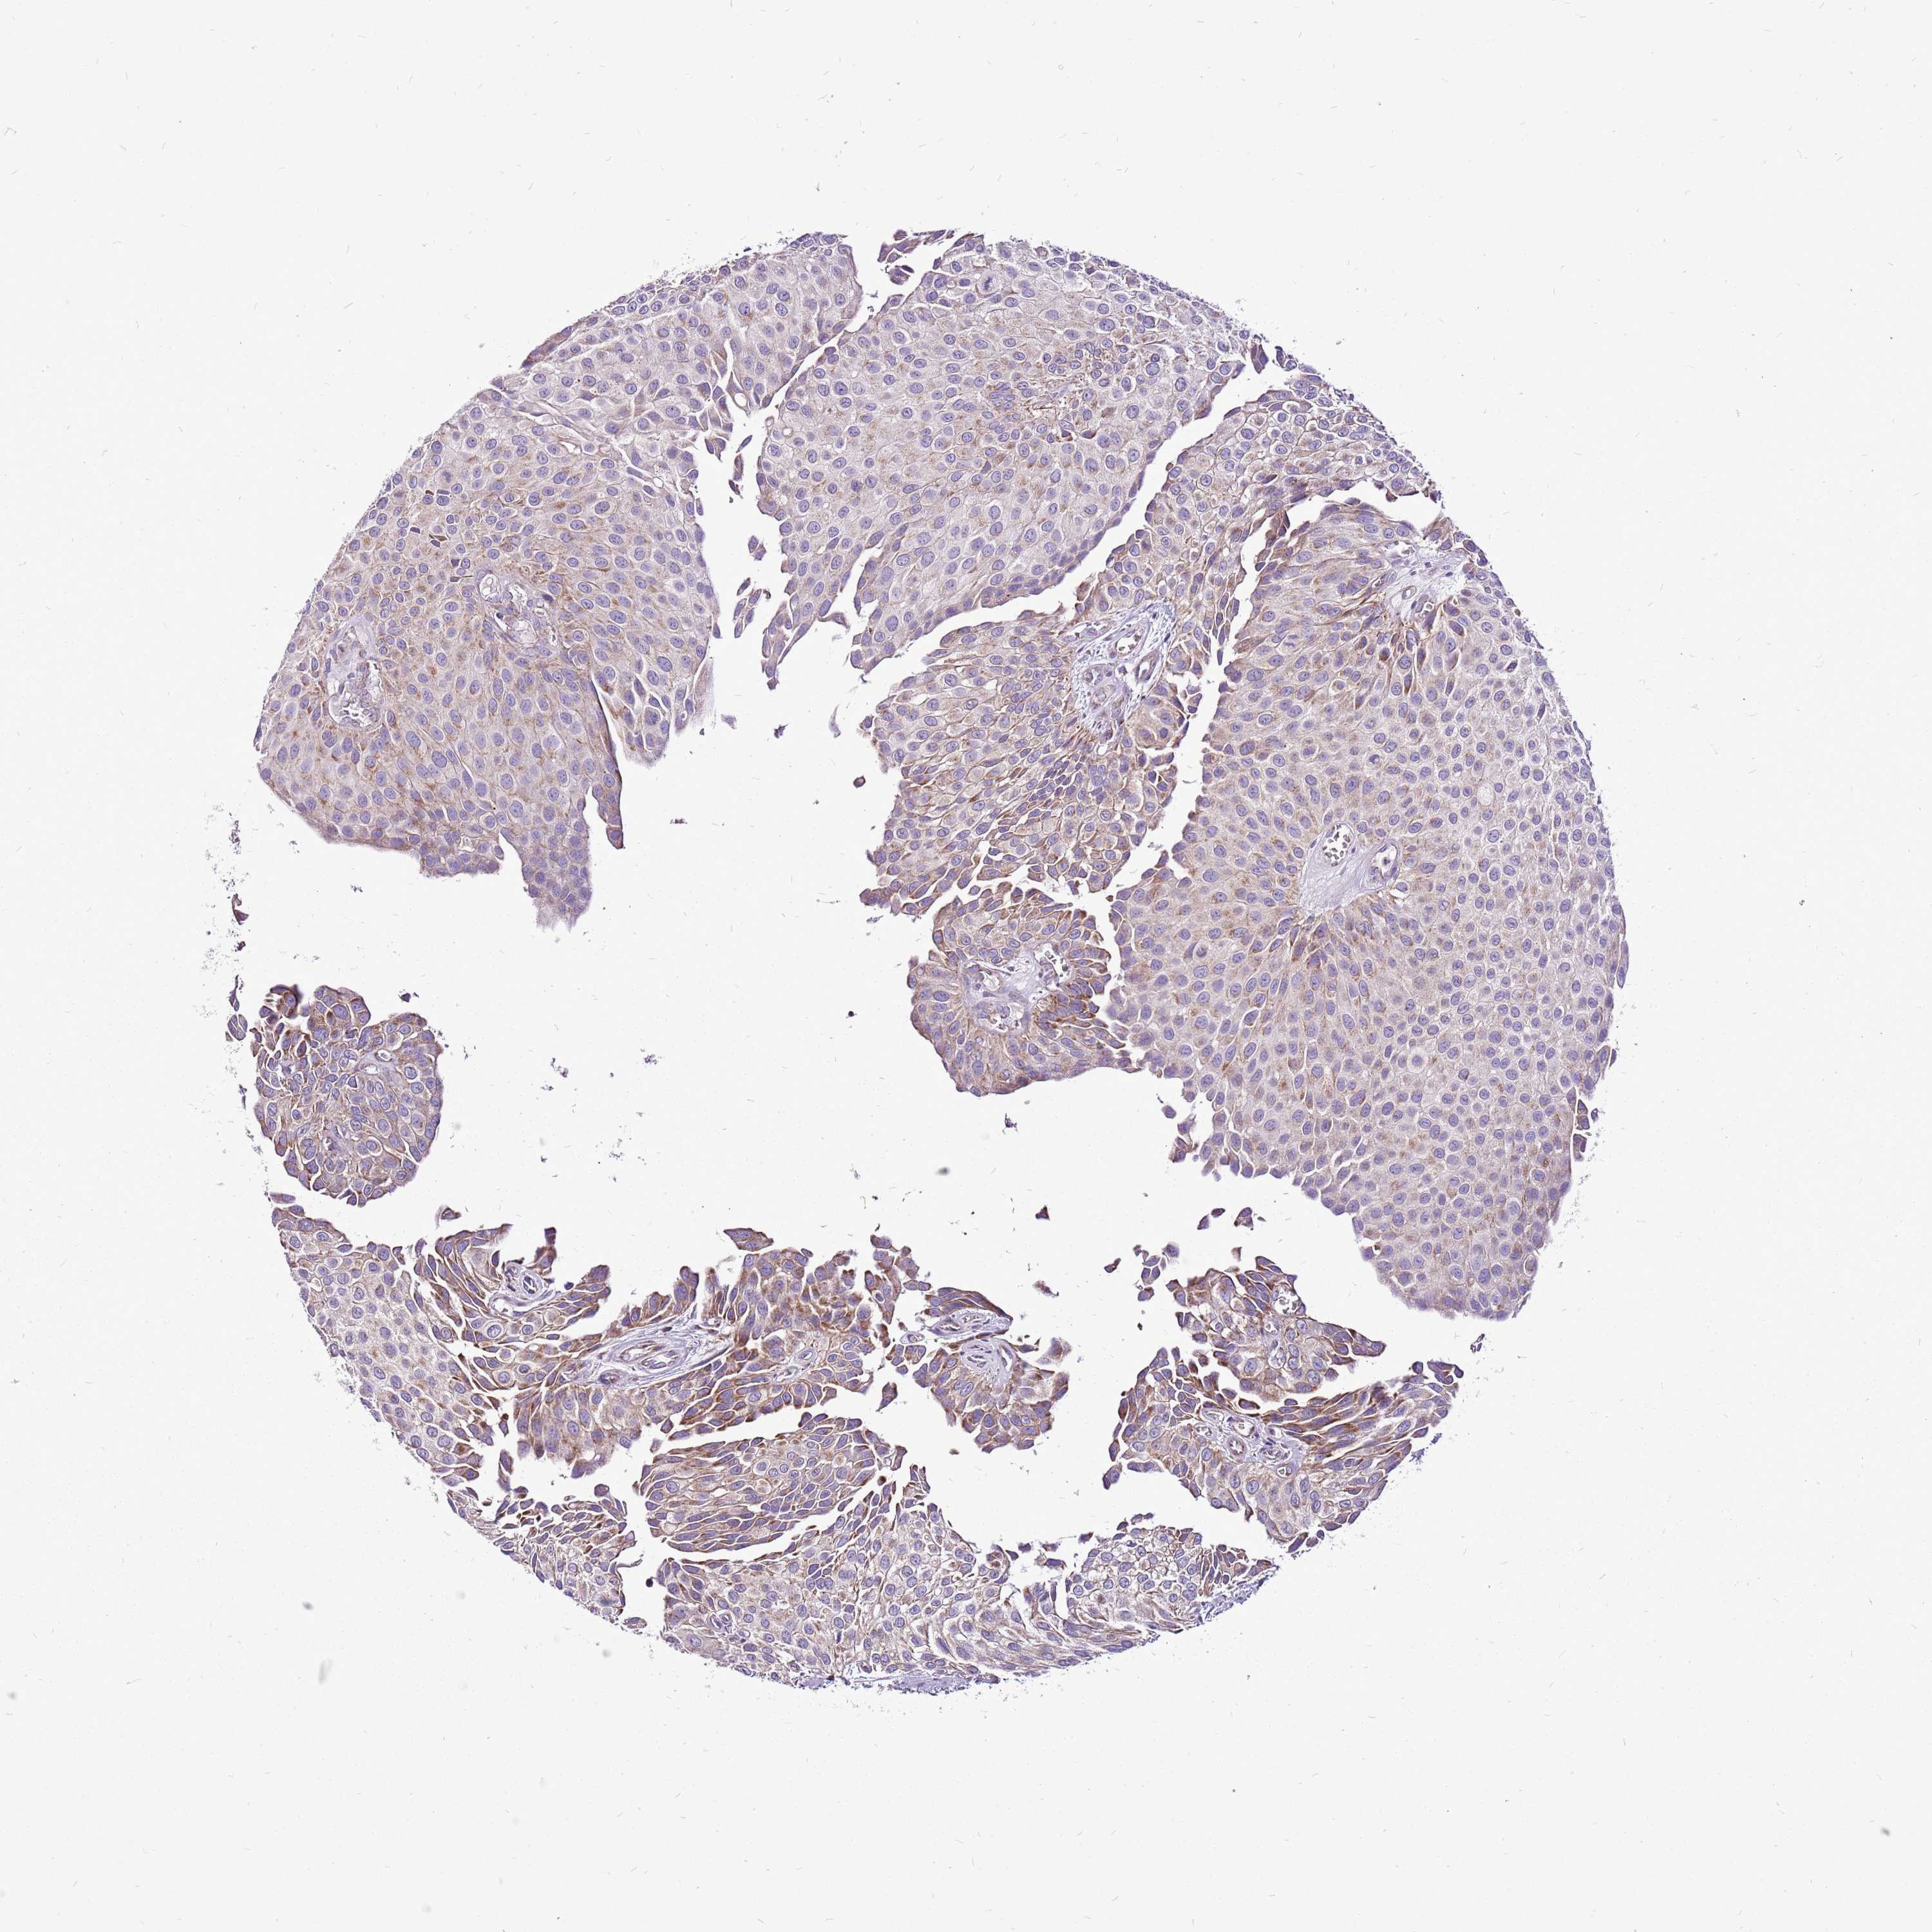

UROTHELIAL CANCER - Protein expressioni

A mouse-over function shows sample information and annotation data. Click on an image to view it in a full screen mode. Samples can be filtered based on level of antibody staining by selecting one or several of the following categories: high, medium, low and not detected. The assay and annotation is described here.

Antibody stainingi

Antibody staining in the annotated cell types in the current human tissue is reported as not detected, low, medium, or high, based on conventional immunohistochemistry profiling in selected tissues. This score is based on the combination of the staining intensity and fraction of stained cells.

Each image is clickable and will lead to virtual microscopy that enables deeper exploration of all samples and also displays staining intensity scores, fraction scores and subcellular localization as well as patient and tissue information for each sample.

Antibody HPA043252

Antibody HPA048492

Urothelial carcinoma, High grade

Urothelial carcinoma, Low grade